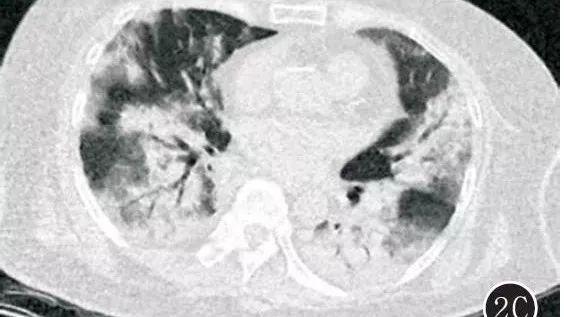

禽流感肺炎CT是啥样,不会诊断要出事! 医学界影像诊断与介入频道 · 公众号 · 医学 · 7 年前 · |

流感不是问题,关键是病毒性肺炎在搞事! 医学界影像诊断与介入频道 · 公众号 · 医学 · 7 年前 · |